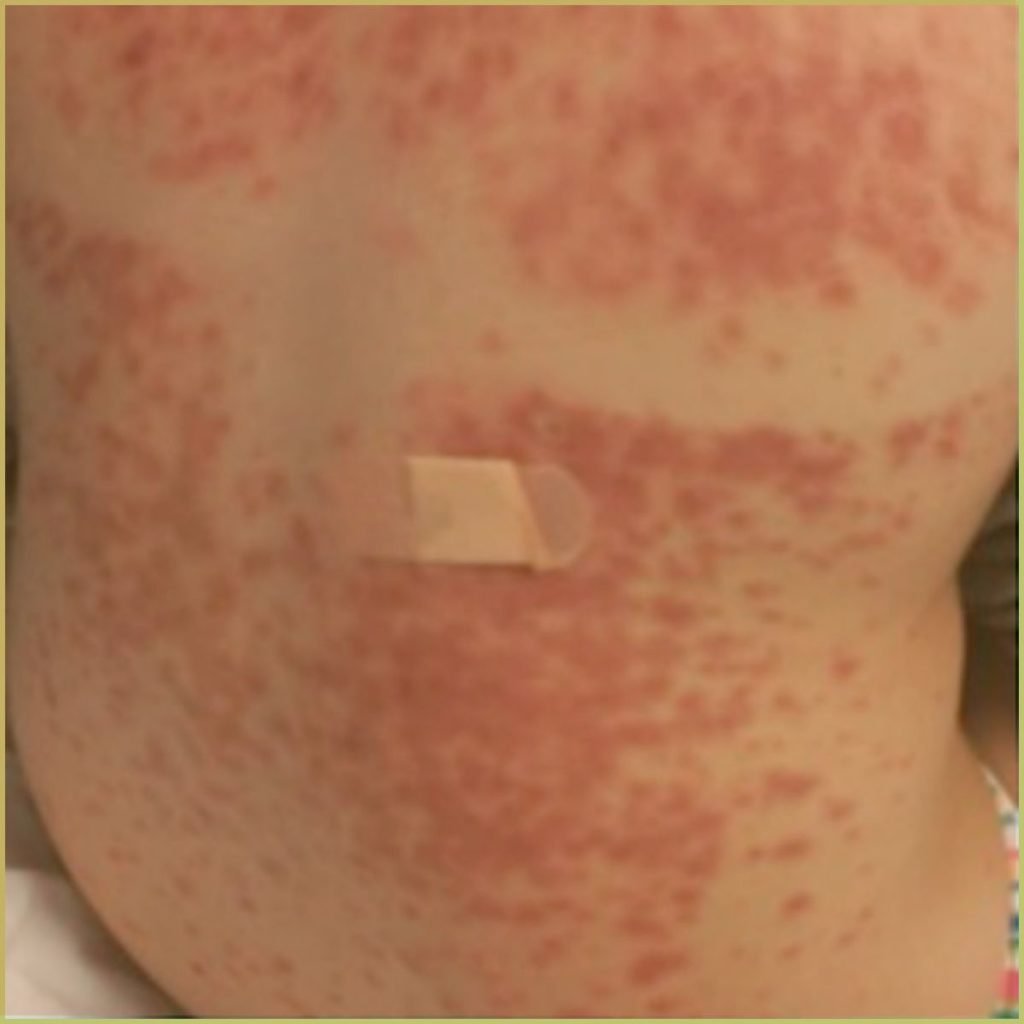

ERYTHEMA MULTIFORME

Erythema Multiforme is an cell-mediated auto-immune disorder, possibly caused by the deposition of immune complexes in the superficial layers of the skin and mucous membranes. It has been known to be associated with certain infections (herpes simplex virus, mycoplasma pneumoniae, cytomegalovirus, Epstein-Barr virus, influenza virus), a wide variety of medications (antibiotics, antiepileptics, non-steroidal anti-inflammatory drugs, statins, vaccines) and other medical conditions (inflammatory bowel disease, malignancy, menstruation). Erythema multiforme can be confused with the more serious Stevens-Johnson syndrome. The common clinical presentation includes:

- Target-like lesions (may be called iris lesions).

- Pink or red papules which can become plaques.

- Lesions on the hands, feet, arms and legs are common. Trunk less so.

- Early mucosal lesions are macular, erythematous, and occasionally bullous.

- Genital and ocular lesions may be present.

- Symptomatic, usually burning or itching. Itching can be very severe.

Diagnosis is usually based on the lesion history and clinical presentation only. If a biopsy is necessary, microscopic findings may include:

- Bulla formation visible in conventional and electron-microscopy.

- Edema in the papillary layer.

- Dermal inflammatory infiltrates consist of lymphocytes and histiocytes.

Your differential diagnosis should include:

- Acute herpetic gingivostomatitis.

- Pemphigus vulgaris.

- Major aphthous ulcers.

- Erosive lichen planus.

- Mucous membrane pemphigoid.

Treatment varies depending on the severity, but may include:

- Identification and elimination of predisposing factor(s).

- Mild form – palliative care only.

- Severe form – systemic corticosteroids and parenteral fluid replacement.

- In the case of a viral trigger, antiviral medications.